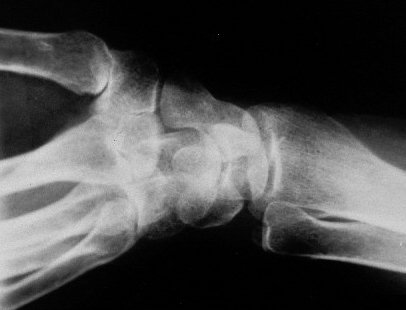

Standard Xray view: Oblique wrist

Xray beam angle 90 degrees.